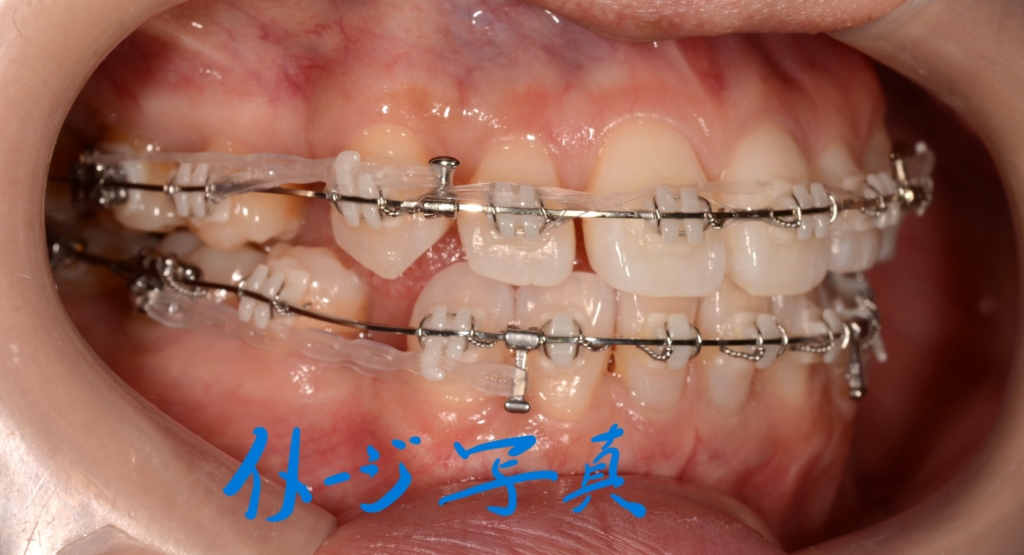

【まだ出っ歯が残る】

前歯のガタガタ(叢生)を解消してきれいに並べて、できるだけ引っ込めたのですが、元々の噛み合わせが上顎前突であったため、どうしても出っ歯が残ってしまいました。

単純に歯並びと噛み合わせを治すだけなら、やりようはあったのですが、できるだけ口元も引っ込めてあげたい!という願いがあったので、引っ込められる分引っ込めて足りない分は後で歯並びごとプラスアルファ―引っ込めよう!という作戦で進めています。

予定通り上顎の口蓋にアンカースクリューを植立しました。

あらためて上顎に、「PLAS」と「パラタルバー」を装着して、上の歯列全体を後方へ押して引っ込めて行きます。